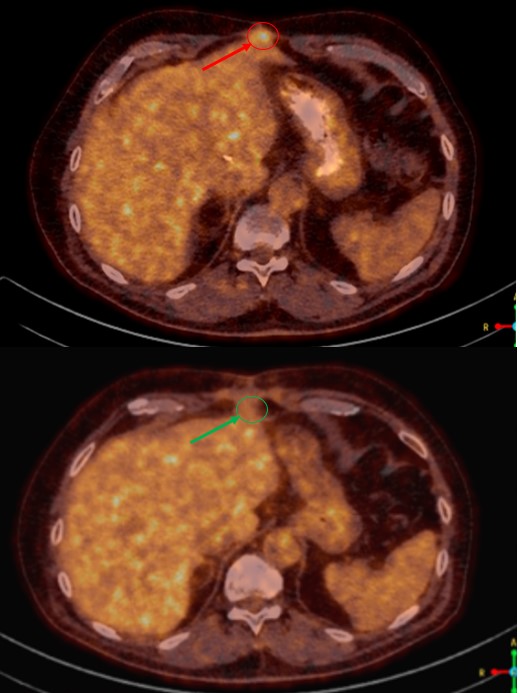

SABR meta pulmonis dex et hepatis, SB Radiochirurgia, 7.5.2022.

Rezultat – 13 mjeseci nakon RK

Potpuni nestanak tretirane lezije